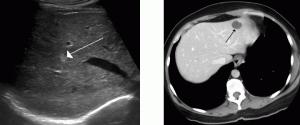

Το υπερηχοτομογράφημα δίνει χαρακτηριστική εικόνα,με σχετικά έντονη ηχογένεια,η οποία οφείλεται στις πολλαπλές ανακλάσεις,αποτέλεσμα της παρουσίας των πολλαπλών αγγείων που περιέχει αυτός ο όγκος.

Το αιμαγγείωμα στην αξονική τομογρφία,χωρίς την ενδοφλέβια χορήγηση σκιαγραφικής ουσίας,εμφανίζεται ώς υποπυκνοτική περιοχή,ενώ μετά την ενδοφλέβια χορήγηση σκιαγραφικής ουσίας παρουσιάζει έντονο εμπλουτισμό που αρχίζει πρώτα από την περιφέρεια.Σε καθυστερημένες τομές σκιαγραφείται χαρακτηριστικά και το κέντρο του καλοήθους αυτού όγκου.Η διάγνωση επιβεβαιώνεται με την αρτηριογραφία,καθώς βλέπουμε πολλα μικρά ελικοειδή ή στρογγυλά αγγεία,στα οποία παραμένει η σκιαγραφική ουσία για χρονικό διάστημα 20-40 δευτερολέπτων.